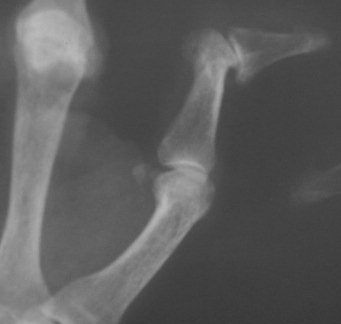

Clinical Example: Rheumatoid arthritis

rheumatoid hand